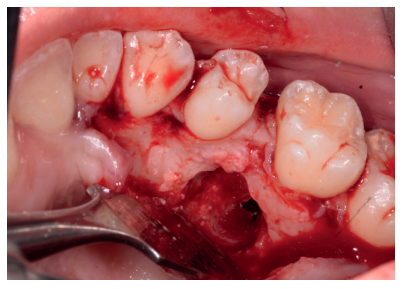

Una vez suturada la herida, se procedió a la extracción del premolar retenido en posición 2.5, para lo cual, tras el bloqueo anestésico de los nervios alveolares superiores posterior, medio y anterior y del nasopalatino y palatino mayor, se realizó una incisión festoneada lineal en la mucosa palatina, y un despegamiento mucoperióstico desde distal del primer molar superior izquierdo hasta distal del incisivo lateral superior izquierdo (Figura 9). Tras el despegamiento, se realizaron las maniobras de ostectomía con pieza de mano y fresa de carburo de tungsteno, la odontosección coronal, y la exodoncia del fragmento coronal y radicular (Figura 10). Al observar la cavidad resultante (Figura 11), se apreció una perforación en la membrana del seno maxilar (Figura 12), en la que se colocó una membrana reabsorbible de colágeno (XFina, Osteógenos®, Madrid, España), de manera previa a la colocación del injerto de dentina (Figura 13). Se le hizo morder al paciente una gasa estéril empapada en clorhexidina al 0,12%, durante la preparación del material de injerto.

Los fragmentos coronal y radicular procedentes del tercer molar inferior y del premolar superior se limpiaron de restos de tejidos blandos y, secos, se introdujeron en la máquina Smart Dentin Grinder® (Kometa Bio, BIONER, España), tal y como aparece en la Figura 14. Tras un ciclo de triturado de 3 segundos, y otro de tamizado de 20 segundos, el material obtenido se limpió con la primera solución durante 12 minutos, y después durante 3 minutos con la segunda solución (Figura 15), para después transportar el material de injerto al alveolo, con presión controlada (Figura 16). Una vez compactado, se colocó una membrana de colágeno (Figura 17) y se suturó la herida con seda de 4/0, mediante puntos periodontales en las papilas (Figura 18). Se realizó una radiografía panorámica en el postoperatorio inmediato (Figura 19).